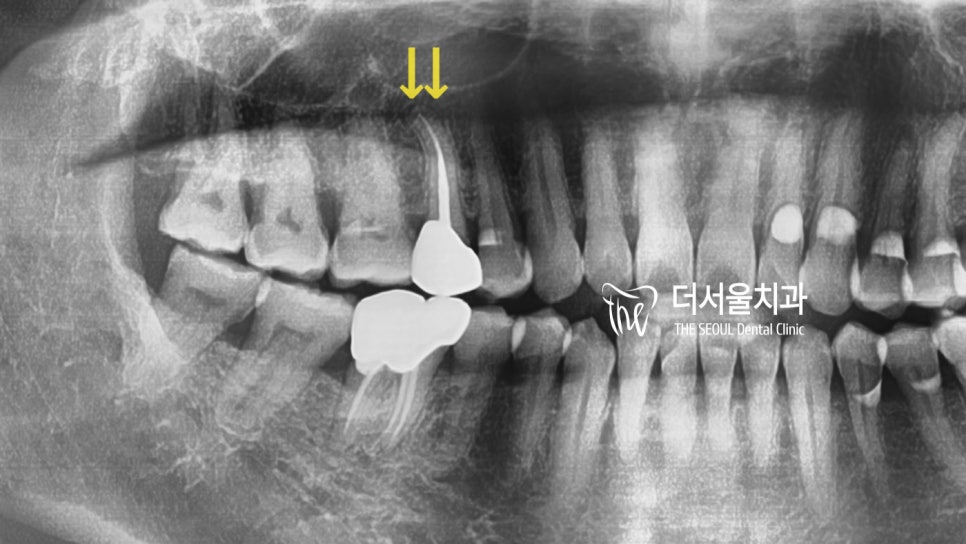

검진을 진행하여 확인해 보니

뿌리에 염증이 잡힌

치근단염이 생긴 것으로 확인되었는데요.

이전에 씌워놓은 골드 크라운 하방으로

이차적인 문제가 발생하여

이렇게 뿌리 끝까지 감염이 된 것으로

추측을 할 수 있었습니다.